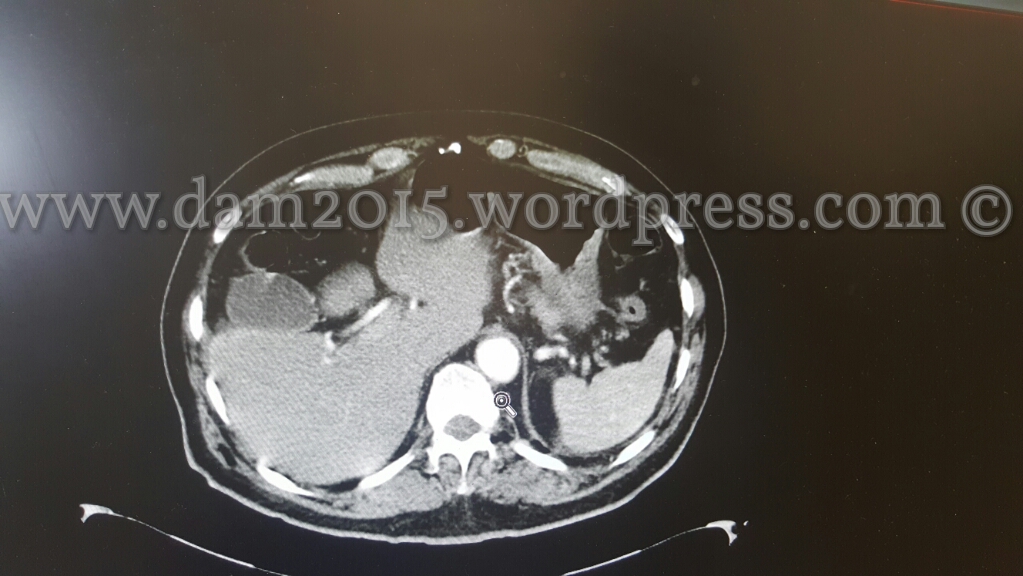

Paziente uomo, 75 aa.

Sospetta diverticolite.

Reperto occasionale, durante esecuzione di angio-TC addome, di trasposizione del fegato che risulta ruotato di 180°.